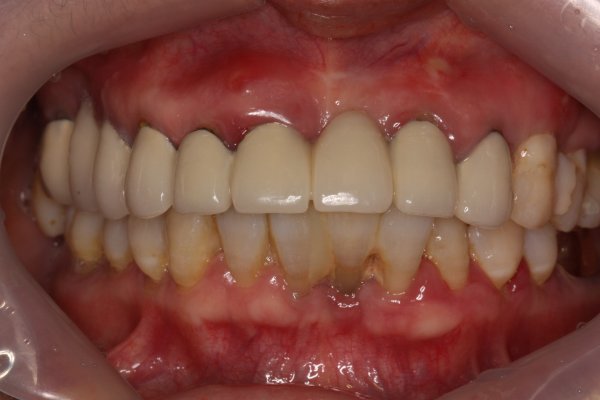

2~3mm정도 남은 잇몸뼈 상태에서 상악동거상술 뼈이식을 진행하여 안정적인 사이즈의 임플란트 식립에 성공